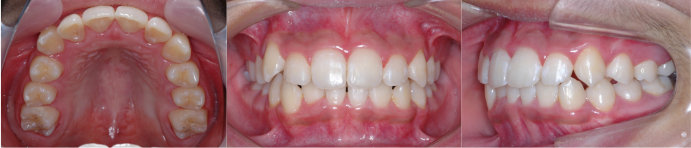

| Case4 |

| 前歯のガタガタ |

| <治療前> |

| <治療後> |

| 主訴 |

上の前歯がガタガタしている |

| 診断名 |

上顎前歯の重度の叢生、下顎前歯の中程度の叢生 |

| 年齢 |

8歳 |

| 使用装置 |

マルチブラケット装置 |

| 抜歯部位 |

永久歯の抜歯は無し |

| 治療期間 |

3年9か月 |

| 治療費概算 |

検査・診断料:5万円+税 装置・技術料:25万円+税 おおよそ1か月ごとの処置・管理料:5,000円+税 保定装置料:5万円+税 |

| リスク・副作用 |

う蝕 |